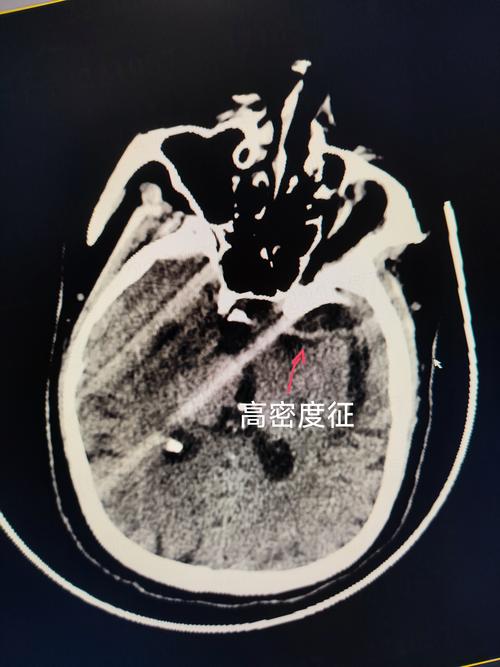

- 过程:当这些小血管完全堵塞时,它所供应的那一小块脑组织就会缺血、坏死,形成一个很小的“梗塞灶”,由于这些梗塞灶通常位于脑组织深处,坏死组织被清除后,会留下一个小空腔,所以被称为“腔隙性梗塞”,其影像学表现就是“腔梗灶”。

- 特点:单个腔梗灶通常非常小(直径一般小于1.5厘米),引起的症状可能很轻微,甚至没有任何症状,因此被称为“静息性脑梗塞”或“无症状性脑梗塞”。